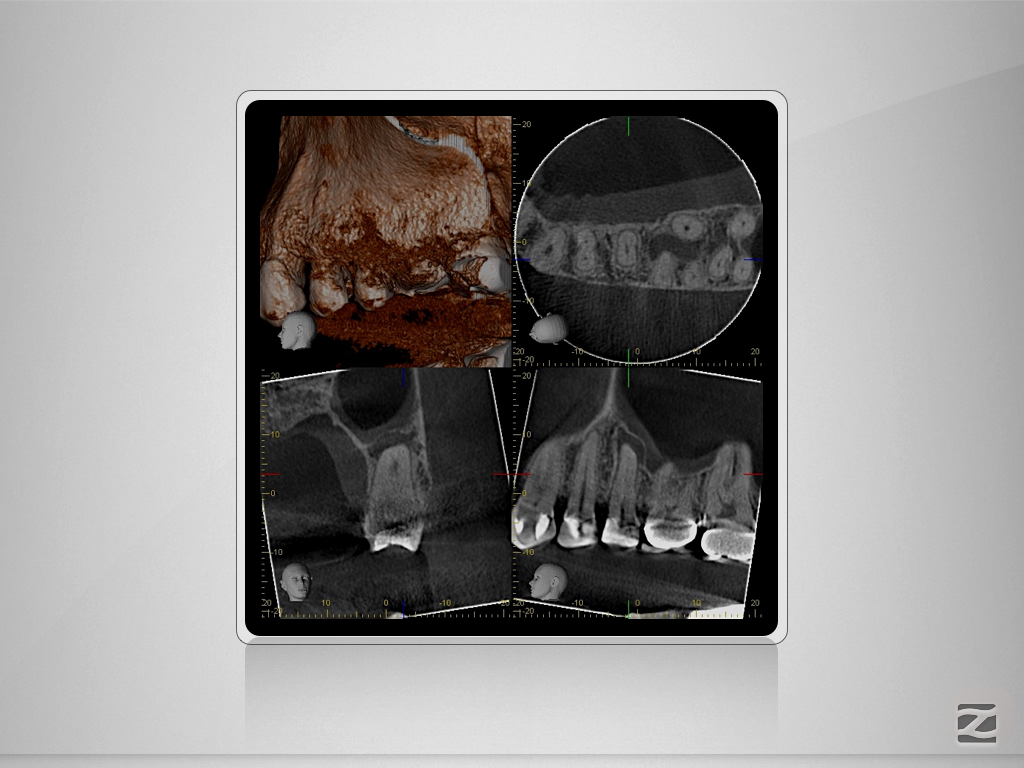

25D.004

Tiefe Gabelung